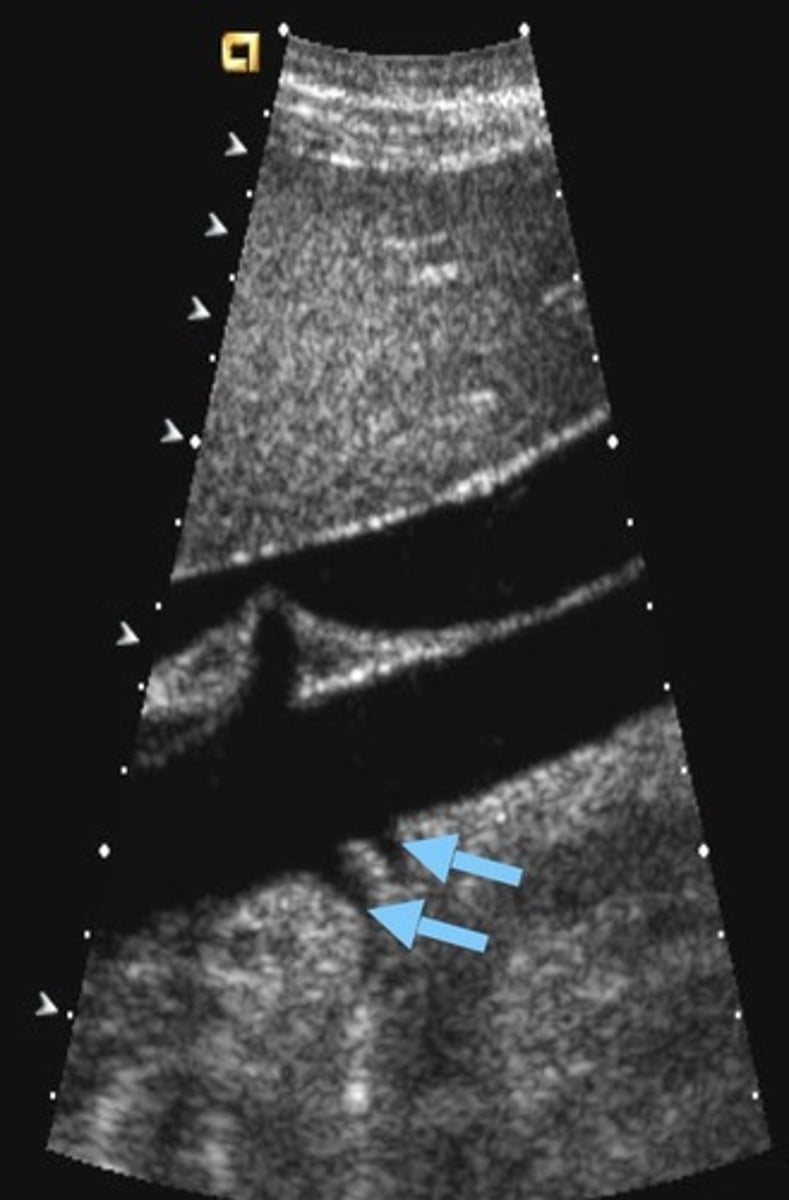

Sonographic Appearance of Renal Vein Thrombosis

Enlarged kidney

Enlarged vein with internal echoes

Lack of color fill

Biphasic/high resistant arterial signal